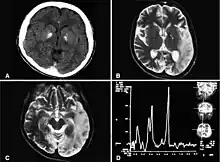

Neuroimaging of lesions in the basal ganglia

Most research in psychological fields regarding amotivational syndrome caused by SSRI treatment has revolved around case studies and anecdotal reports to understand how SSRI medication influences levels of motivation and apathy in patients.[12] There is considerable overlap in the clinical presentations of apathy and motivation and depression. Many patients with amotivational or apathy syndrome reported that they felt a lack of motivation that was unlike what they had sometimes experienced during previous episodes or depression, or that their feelings of apathy had no link to depression. Apathy syndrome has also been reported in a number of patients that have received or are receiving selective serotonin reuptake inhibitor (SSRI) treatment over the last decade, which has also been linked to a deficit in the performance and activities of daily living, signaling a functional decline.[12] It is a common behavioural problem that often goes undiagnosed and untreated, which is why it is considered to be clinical significant. Neuropsychological research has shown that a common feature of amotivational syndrome involves the presence of lesions and other abnormalities in the circulation of the frontal lobe.[12] Neuroimaging studies of clinical populations have also reported correlations between apathy and structural and functional changes in the frontal lobe in the anterior cingulate gyrus and subregions of the basal ganglia.[12] Recent case-control studies have also reported that apathy has appeared to be greater in patients who were treated with SSRI medication compared to patients who were not.[12] Current findings are consistent with other findings supporting the correlation of SSRI and apathy due to the occurrence of abnormalities found within various regions of the frontal lobe.[12] Though amotivational syndrome has been an emerging concern for pharmacotherapeutic industries to consider, there is still a growing body of empirical investigations that need to continue in order for the development of novel therapeutic interventions to improve, as well as treatment.[12] Currently, empirical studies are limited and there is not a substantial enough amount of research to fully understand the link between frontal lobe abnormalities caused by SSRIs and thus resulting in amotivational syndrome. There is a lack of large-scale clinical studies that focus on the prevalence of SSRI-induced amotivational syndrome with regards to emotional blunting and apathy in both psychiatric or primary care populations, despite the high prescription rates for SSRI medication.[5] There are also no current clinically popular scales to measure and assess SSRI-induced apathy. The Oxford Questionnaire of Emotional Side Effects of Antidepressants (OQESA) is a scale under development and presents a 26-item, Likert-style, self-report scale that aims to understand respondents’ emotional experiences such as a general reduction in emotions, a reduction in positive emotions, emotional detachment and blunting, and feelings of not caring.[5] Respondents are also asked to what extent they believe their antidepressant is responsible for these emotional symptoms.[5]